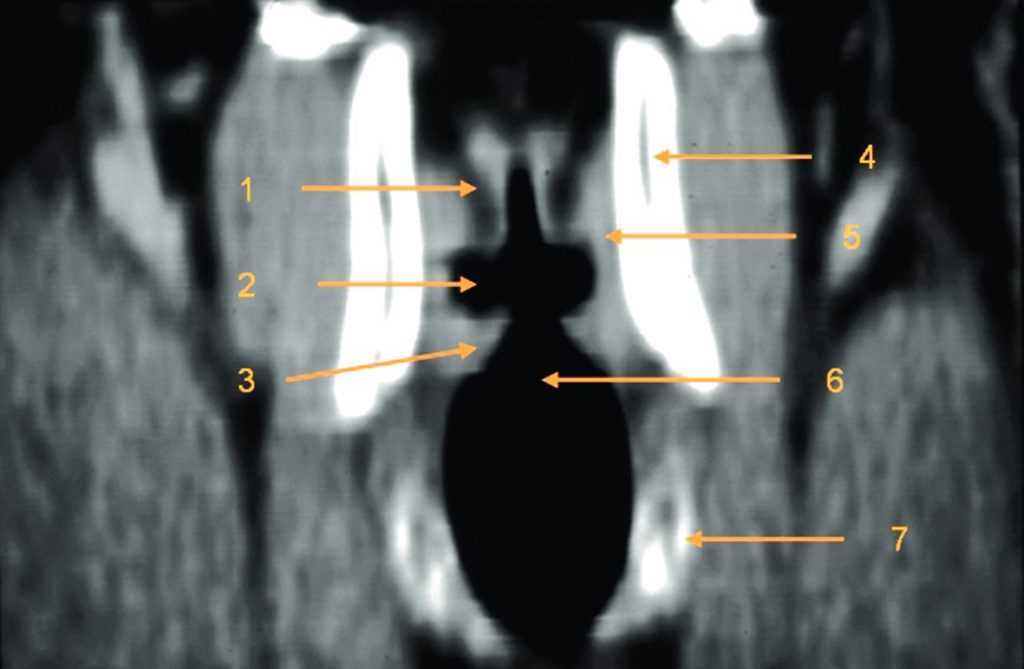

Fig. 62.3 Temporal droit : scanner, coupe frontale.

1. Paroi osseuse latérale du récessus épitympanique. 2. Méat acoustique externe. 3. Tegmen tympani. 4. Tête du malléus. 5. Incus. 6. Cochlée. 7. Canal carotidien. 8. Nerf facial, 2e portion. 9. Cellules mastoïdiennes.

Source : CERF, CNEBMN, 2022.